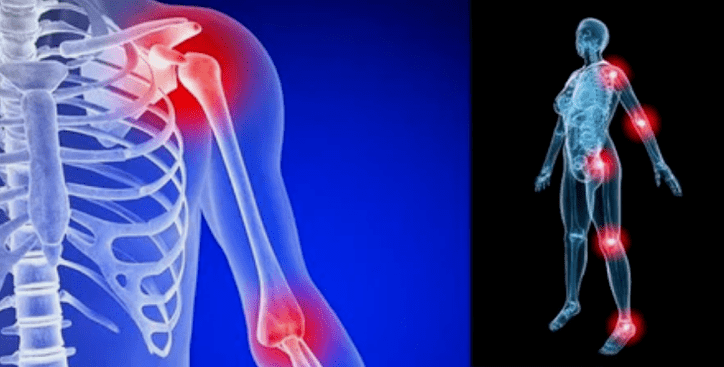

Die Manifestationen der Krankheit unterscheiden sich in Abhängigkeit von der Lage kaum, häufiger spiegeln sich die Zeichen auf den Knien auf den Gelenken der Schulter und der Hüfte aufgrund der hohen Belastung wider.